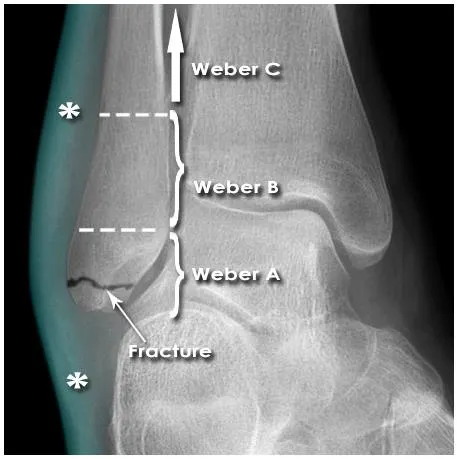

Danis-Weber classification

Defines injury based on level of fibular fracture

A=below tibiotalar joint

No disruption of syndesmosis

Usually stable

B=at level of tibiotalar joint

Partial disruption of syndesmosis

C=above tibiotalar joint

Disrupts syndesmosis to level of fracture

unstable

THE MORE PROXIMAL THE FIBULAR # THE MORE SEVERE THE INJURY

Lateral Malleolar Fracture Danis-Weber A

Mechanism : Supination/adduction (inversion)

Mortise intact

Stable fracture(align normal)

Soft tissue swelling

Treatment : below knee cast